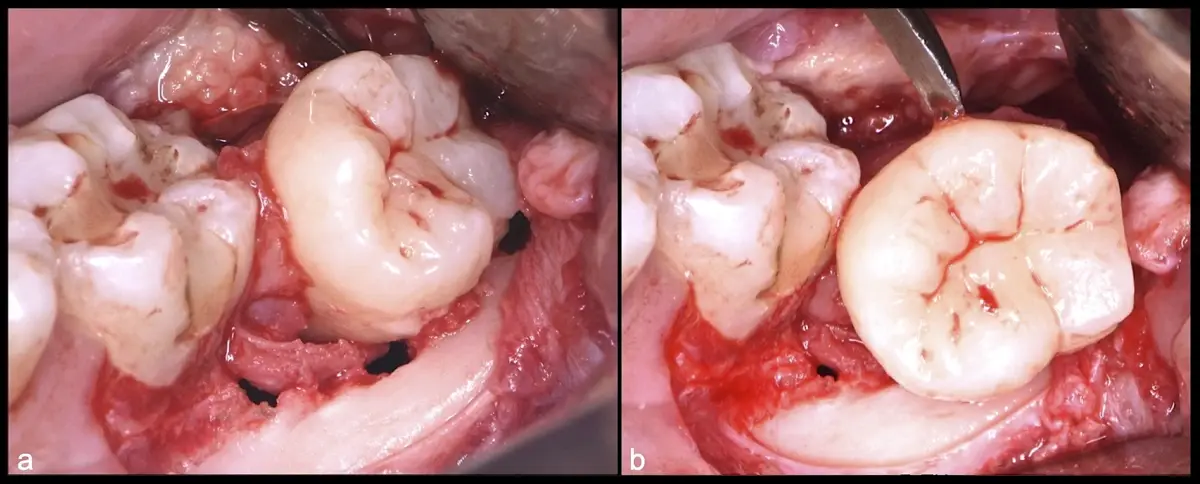

Figura 23. Luxación de pieza 3.8 con botador recto convencional (a). Extracción de pieza 3.8 (b).

Figura 24. Exodoncia de la pieza 3.8 (a). Lecho óseo posterior a la exodoncia pieza 3.8 (b).